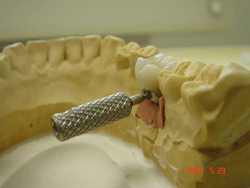

| 左下456番に埋伏歯を避けブリッジタイプのハイブリッドセラミック補綴 |